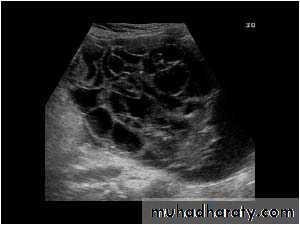

POLYCYSTIC OVARY SYNDROME

Images from women with differing expressions of the four major subtypes of the metabolic syndrome associated with polycystic ovary syndrome (A–D). The images exhibit quite differing ultrasonographic appearances in the size and distribution of follicles within PCOS ovaries. A recent corpus luteum is clearly visible in the ovary in panel (D).

• POLYCYSTIC OVARY SYNDROME

Images from women with differing expressions of the four major subtypes of the metabolic syndrome associated with polycystic ovary syndrome (A–D). The images exhibit quite differing ultrasonographic appearances in the size and distribution of follicles within PCOS ovaries. A recent corpus luteum is clearly visible in the ovary in panel (D).• POLYCYSTIC OVARY SYNDROME

Images from women with differing expressions of the four major subtypes of the metabolic syndrome associated with polycystic ovary syndrome (A–D). The images exhibit quite differing ultrasonographic appearances in the size and distribution of follicles within PCOS ovaries. A recent corpus luteum is clearly visible in the ovary in panel (D).The Oviduct (Fallopian Tube)